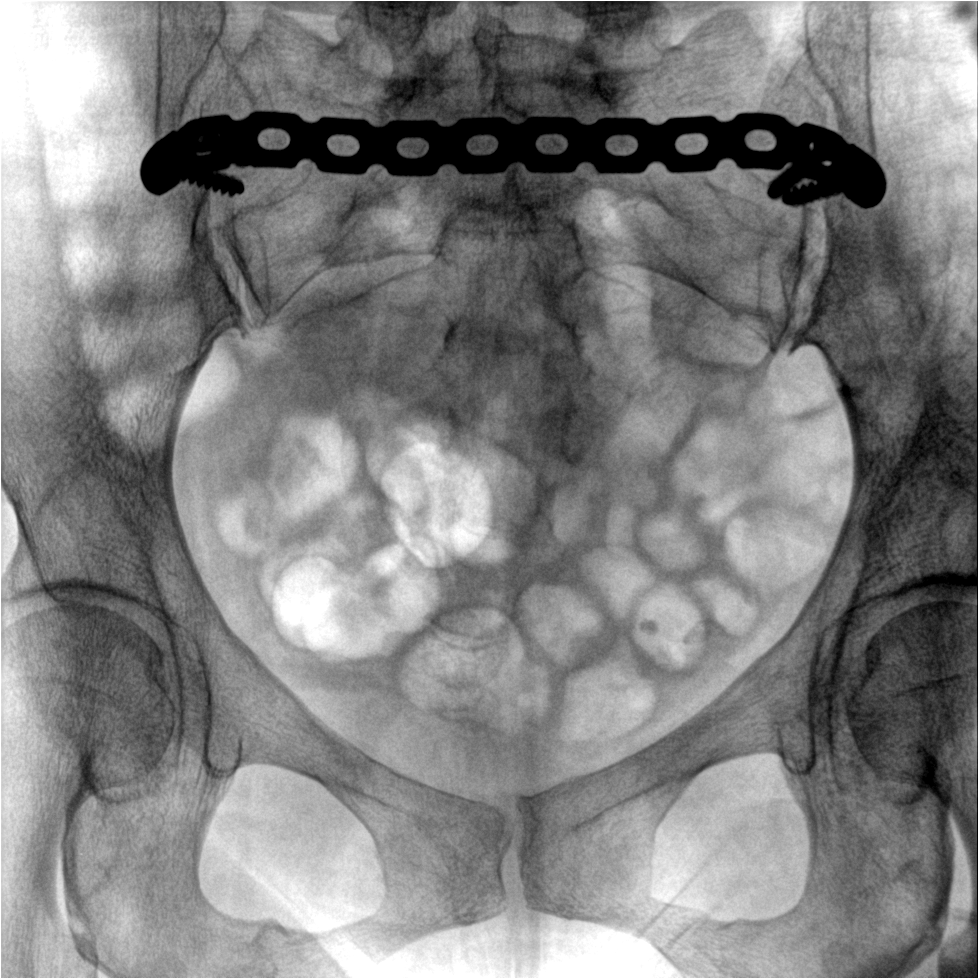

術(shù)中三維成像和橫斷面圖像提供多角度的手術(shù)診斷信息,輔助醫生進(jìn)行術(shù)中評估判斷,諸如骨折復位情況和內植入螺釘的尺寸和位置,輔助手術(shù)更好地完成。

提供更大的術(shù)中三維成像視野,采集更多圖像信息,可一次拍全全段頸椎、全段腰椎、七節胸椎、雙側骶髂關(guān)節、股骨頭及單側盆骨。